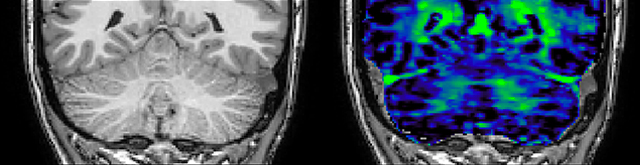

T1 - Weighted, Myelin Water Fraction Superimposed

MWI Spinal cord coverage

Spinal cord coverage

MWI Smaller, more isotropic voxels

Smaller, more isotropic voxels

MWI Excellent detail in quantitative maps

Excellent detail in quantitative maps

Images courtesy of Adam Dvorak, Department of Physics and Astronomy, University of British Columbia

20%

Myelin water fraction

0%

of limiting MWI to the brain, even without the cerebellum, we can now spend about the same amount of time and scan the whole brain and the cervical spinal cord, which is a huge boost for us.”

Dr. Rauscher says, “For MWI we perform 3D T2 with 32 or more echoes. This used to take a long time, but with Compressed SENSE we can decrease this to ten minutes for the whole head. Because of the large field of view (FOV) on the readout direction, we even get information from the brainstem, which we previously missed when we were using the GRASE approach. Having the whole head scan is nice because it has spatial resolution, orientation and FOV that are comparable to the standard 3D clinical MS scans, including the FLAIR and 3D T2, and a 3D T1 for brain volume.”

Dr. Rauscher says, “With better gradients we can use a shorter echo spacing on the spin echo, so we get better sampling of the rapidly decaying myelin signal, which typically has T2 of around 10-20 milliseconds at 3 Tesla. If we can reduce echo spacing from about 8 to 5-6 milliseconds, we get a much better sampling of the short decay component and increase our SNR, which is a big advantage. The same is true for multi-echo gradient echo which we use for susceptibility mapping and for mapping venous vessels in MS.”